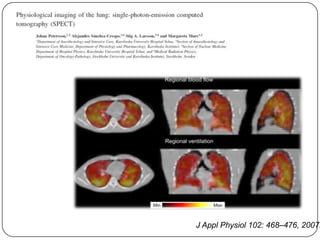

Fluxo sanguíneo pulmonar e

ventilação regional

overventilation

overperfusion

J Appl Physiol 81:1822-1833, 19

J Appl Physiol 102: 468–476, 2007.

Fluxo sanguíneo pulmonar e ventilação regional • Ventilação e fluxo sanguíneo são dependentes da gravidade; RELAÇÃO DE VENTILAÇÃO-PERFUSÃO • Fluxo sanguíneo 5x maior ápice que base e ventilação 2x. Há variação regional gravidade dependente da Va/Q • Fluxo sanguíneo é proporcionalmente maior na base e ventilação maior no ápice

Fluxo sanguíneo pulmonare ventilação regional overventilation overperfusion